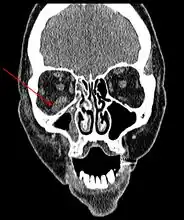

Imaging

Imaging is often performed, such as CT scan of lungs and sinuses.[38] Signs on chest CT scans, such as nodules, cavities, halo signs, pleural effusion and wedge-shaped shadows, showing invasion of blood vessels may suggest a fungal infection, but does not confirm mucormycosis.[16] A reverse halo sign in a person with a blood cancer and low neutrophil count, is highly suggestive of mucormycosis.[16] CT scan images of mucormycosis can be useful to distinguish mucormycosis of the orbit and cellulitis of the orbit, but imaging may look identical to those of aspergillosis.[16] MRI may also be useful.[39]

CT head (axial): invasion of right maxillary sinus (presented with double vision, swollen painful eye).

CT head (coronal) of same person.